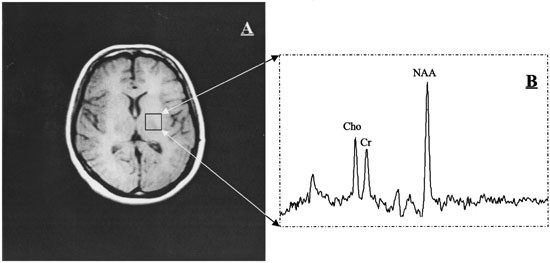

March 21 2017 A new imaging biomarker may help predict which children will take longer to recover from a traumatic brain injury TBI according to a preliminary study published online in Neurology. Kontaktinformationen und 5 bewertungen für Open System Imaging in 747 E Union St Pasadena CA anzeigen oder eine Bewertung schreiben. I am extremely nervous around needles and needed to get one for my hip MRI.

Abankunda 36 1 bari kuyivugaho 111 bageze hano. Open System Imaging - Pasadena Pasadena. Open System Imaging - Pasadena. Open System Imaging - Pasadena. Erkunden Sie eine interaktive Karte mit Orten in der Nähe. March 21 2017 A new imaging biomarker may help predict which children will take longer to recover from a traumatic brain injury TBI according to a preliminary study published online in Neurology. April 27 2017.